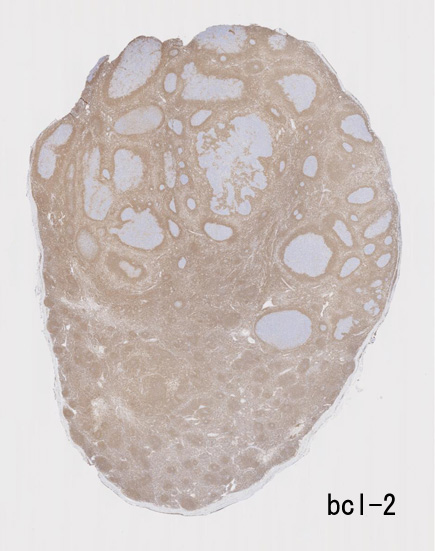

不整形の胚中心(CD20+, CD10+, BCL2-)のまわりにはCD5陽性リンパ球が多く存在してマントル層を形成している. (IgD染色でもマントル層はよく認識できる). 胚中心内のCD5+ cellはfollicular helper T-cellのようです.

大きな胚中心を持つ多数のリンパ濾胞が見られる。胚中心の辺縁は不明瞭でマントル層も薄くなっている。1カ所マントル層リンパ球の侵入によりバラバラになった巨大な胚中心が認められ, macrofollicular patternと記載されるPTGCです。

鑑別にあがるfollicular lymphoma floral variantは全ての濾胞が腫瘍性であり, 本症例では除外可能と考える。

Diagnosis: Reactive lymphadenitis with PTGC